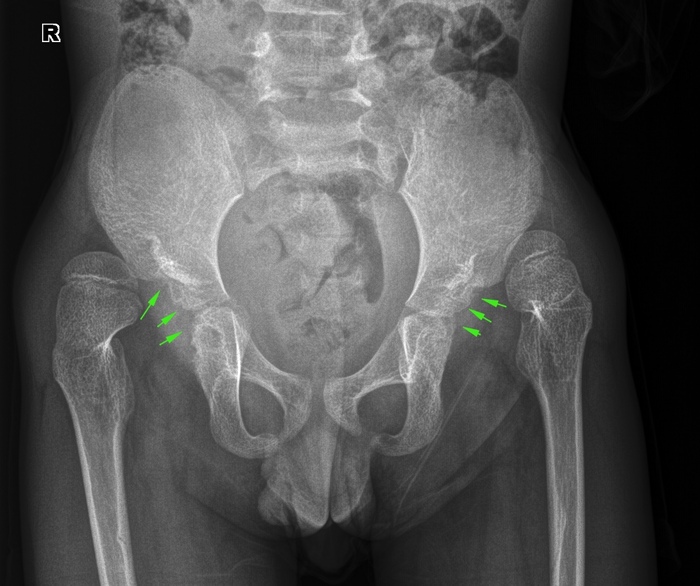

История 6. Дисплазия тазобедренных суставов

Различают несколько стадий формирования дисплазии – подвывих, вывих, высокий вывих. Вот как они выглядят на схеме:

А вот как выглядит на рентгенограмме. Стоит отметить, что обычно дисплазию тазобедренных суставов диагностируют в возрасте до года, но данный снимок пренадлежит мальчику 7 лет. Вполне вероятно, он и раньше делал снимки, но у нас был впервые.

На Rn-граммах тазобедренных в прямой проекции в вертикальном положении, в условиях динамической нерезкости, в атипичной укладке: с небольшим разворотом вправо, определяется двусторонние вывихи тазобедренных суставов на фоне дисплазии крыш вертлужных впадин (вертлужные впадины указаны стрелками). Суставы определяются гораздо выше впадин. Снимки и описание делала моя коллега.